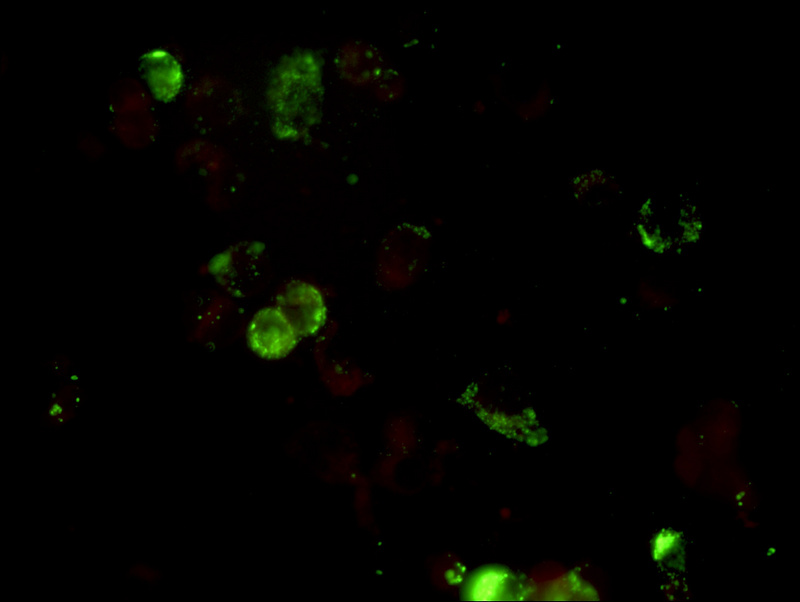

流感疫苗_06.jpg

流感病毒检测阴性

使用荧光显微镜400倍视野观察(40X物镜),甲型流感检测孔位荧光少且弱,视为阴性结果,荧光亮度强数量多,平均每个视野的阳性细胞大于3-5个,就可以判断为阳性。乙型流感另有一个孔位,判断标准和甲型流感一致。

流感疫苗_07.jpg

流感病毒检测阳性

免疫荧光法检测快速,而且准确性高于胶金体法,因此得到越来越多医疗机构的选择。